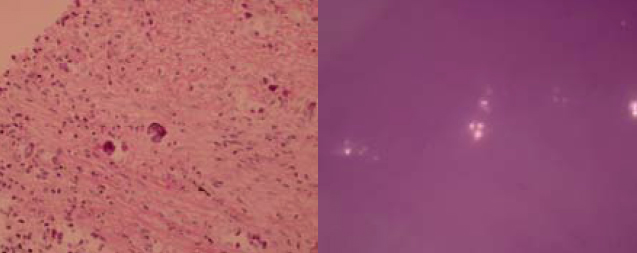

As the condition did not improve and pulmonary tuberculosis was a differential diagnosis with the CXR appearance, empirical anti-tuberculous treatment was started (isoniazid, rifampicin, ethambutol, pyrazinamide) on 4th September 2009. CT-guided biopsy of the lung lesion was subsequently performed. While culture of the biopsy was negative, histology report revealed inflammation, fibrosis, and foreign body giant cell reaction against crystal–like foreign body, nature of which was unknown. It was negative for malignancy and fungal stains (PAS/PASD and Grocott). X-ray microanalysis and the appearance of the crystals under electron microscopy were suggestive of presence of calcium oxalate crystals. (Fig. 2a and 2b) More in-depth history was elicited. Although the patient was a tour guide before the admission, he had worked in a construction site with respirator on for 10 days 8 years ago. He denied history of intravenous drug addiction or inhalational drug abuse. There was no choking on eating. Ophthalmologist was consulted to look for any crystallinopathy or embolism in the fundi, which were absent. Oxalate level in 24-hour urine was 0.32 mmol/day (normal range 0.08-0.49 mmol/day), making possibility of hyperoxaluria less likely.

In our case, we were given the clue of having crystals in the lungs. According to literature, there are only a few types of crystals in lungs. Charcot-Leyden crystals are eosinophilic structures typically rhomboidal or needle-shaped crystalline by-products of eosinophil granules1 and can be found in hyper-eosinophilia states like asthma and fungal infections.1 Calcium salts like calcium oxalate can be found in fungal infections such as aspergillosis and zygomycosis.5,6,7 Intravascular crystal-like embolus is the third type of crystals present in lungs.3 These can arise from vascular manipulations like vascular surgery.3 In patients with crystal-storing histiocytoma, paraprotein accumulation within the cells accounts for the presence of crystals 4

Calcium salts have been found in fungal infections. While they are usually found in aspergillosis, they have also been mentioned in some case reports of zygomycosis.5,6,7 Amongst the calcium salts, calcium oxalate has been the most commonly identified component.5,6,7 In humans, a direct association has been found between oxalate crystal production and Aspergillus niger or less often Aspergillus fumigatus infection.11 It has been reported that calcium oxalate is a fermentation product of Aspergillus species via the tricarboxylic acid cycle.2,11 Such crystals, as suggested by Yoshihisa et. al., could cause damage to the lung tissue.2 Such damage may lead to fatal pulmonary haemorrhage.11 In addition to the lung tissue, it has been reported that calcium oxalate is also present in sputum. Together with serological assays, this might give the hint for early diagnosis of aspergillus pneumonia. 2